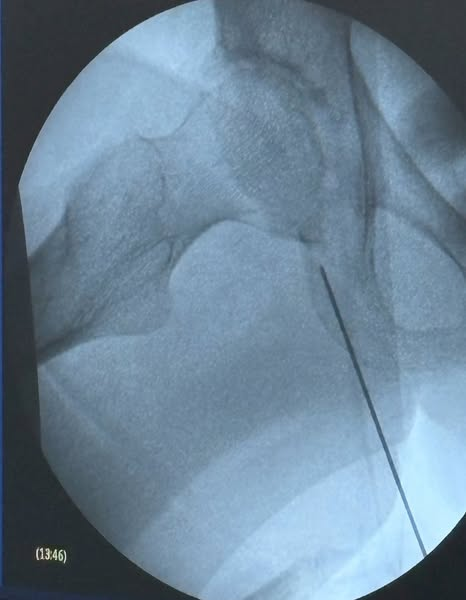

日本初となる股関節へのラジオ波末梢神経焼灼療法成功

日本初となる股関節へのラジオ波末梢神経焼灼療法(ラジオ波治療)が成功いたしました。

変形性股関節症による長年の痛みに悩まれていた患者さまが、治療後より痛みの消失を実感されております。